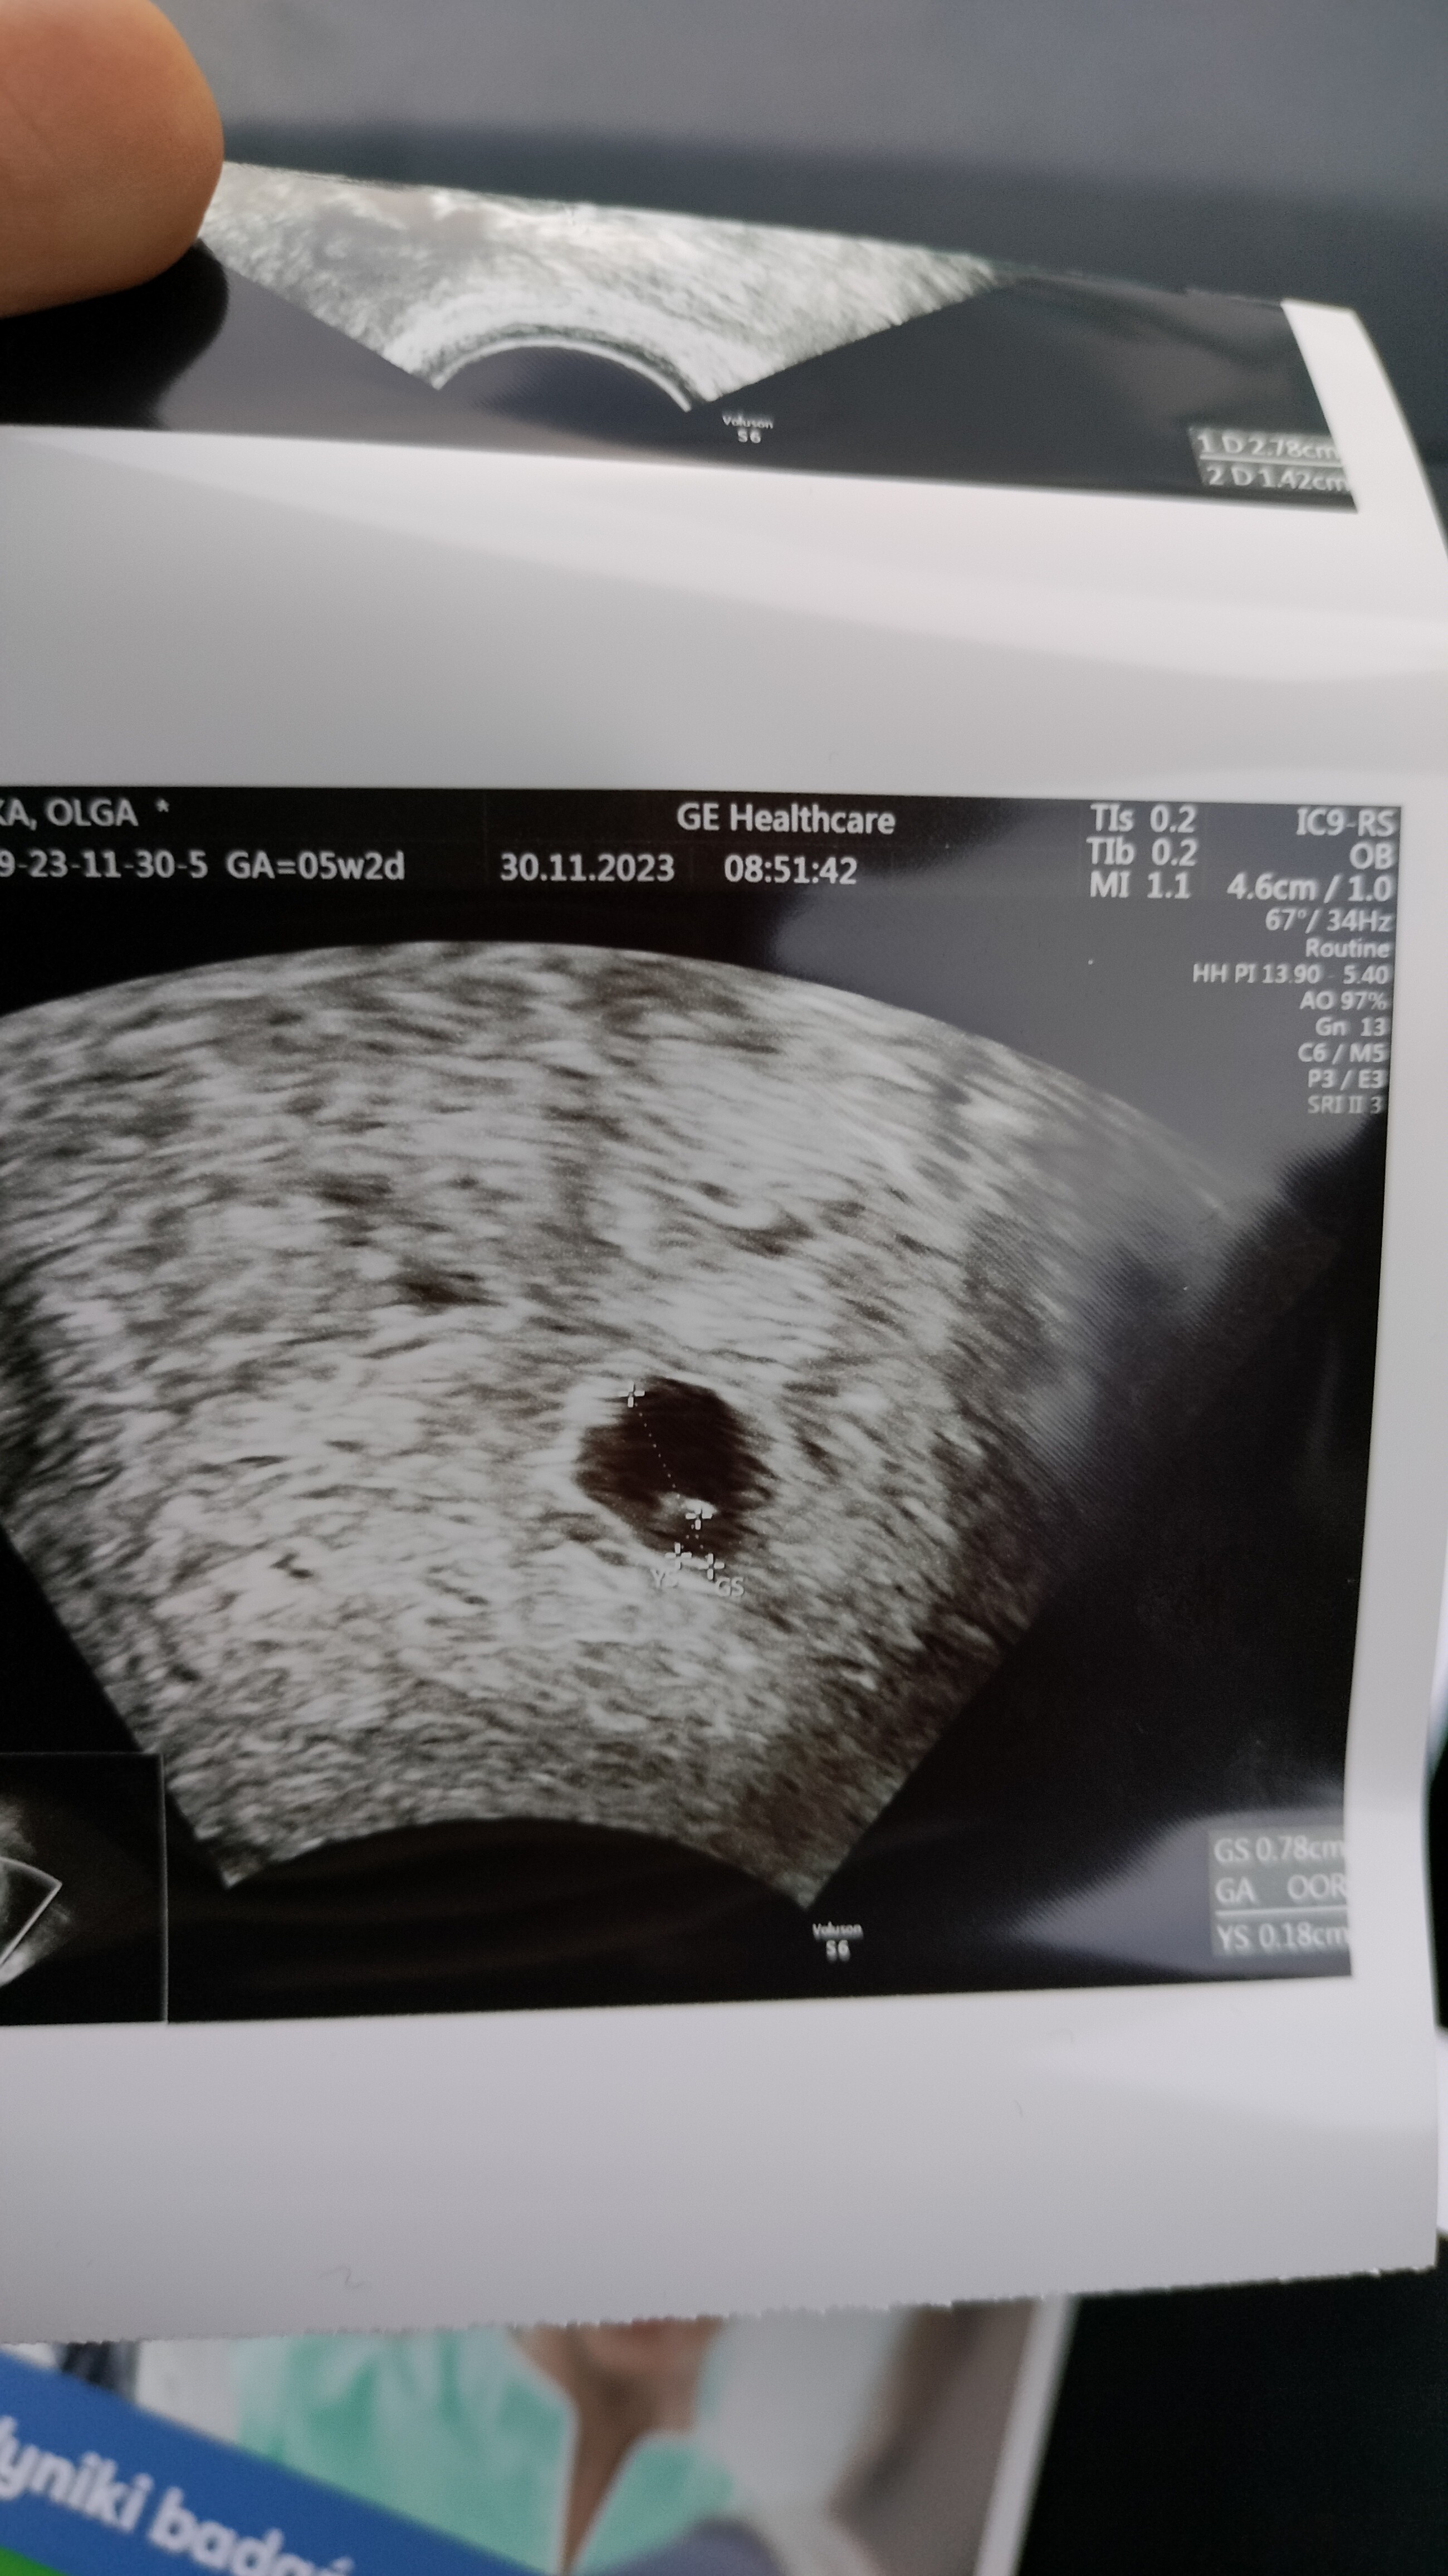

Może to tylko różne odczynniki laboratoryjne?. Dziwne żeby ciąża się rozwijała przy spadającej becie. Trzymam kciuki!Jestem po USG... Pęcherzyk urósł, pojawiło się ciałko żółte... Wszytko się zgadza. Zgłupiałam.

Powtórz betę. Trzymam kciuki żeby to jednak błąd labu był i wszystko jest okJestem po USG... Pęcherzyk urósł, pojawiło się ciałko żółte... Wszytko się zgadza. Zgłupiałam.

Kurcze, oby jednak miało to szczęśliwe zakończenie!Jestem po USG... Pęcherzyk urósł, pojawiło się ciałko żółte... Wszytko się zgadza. Zgłupiałam.